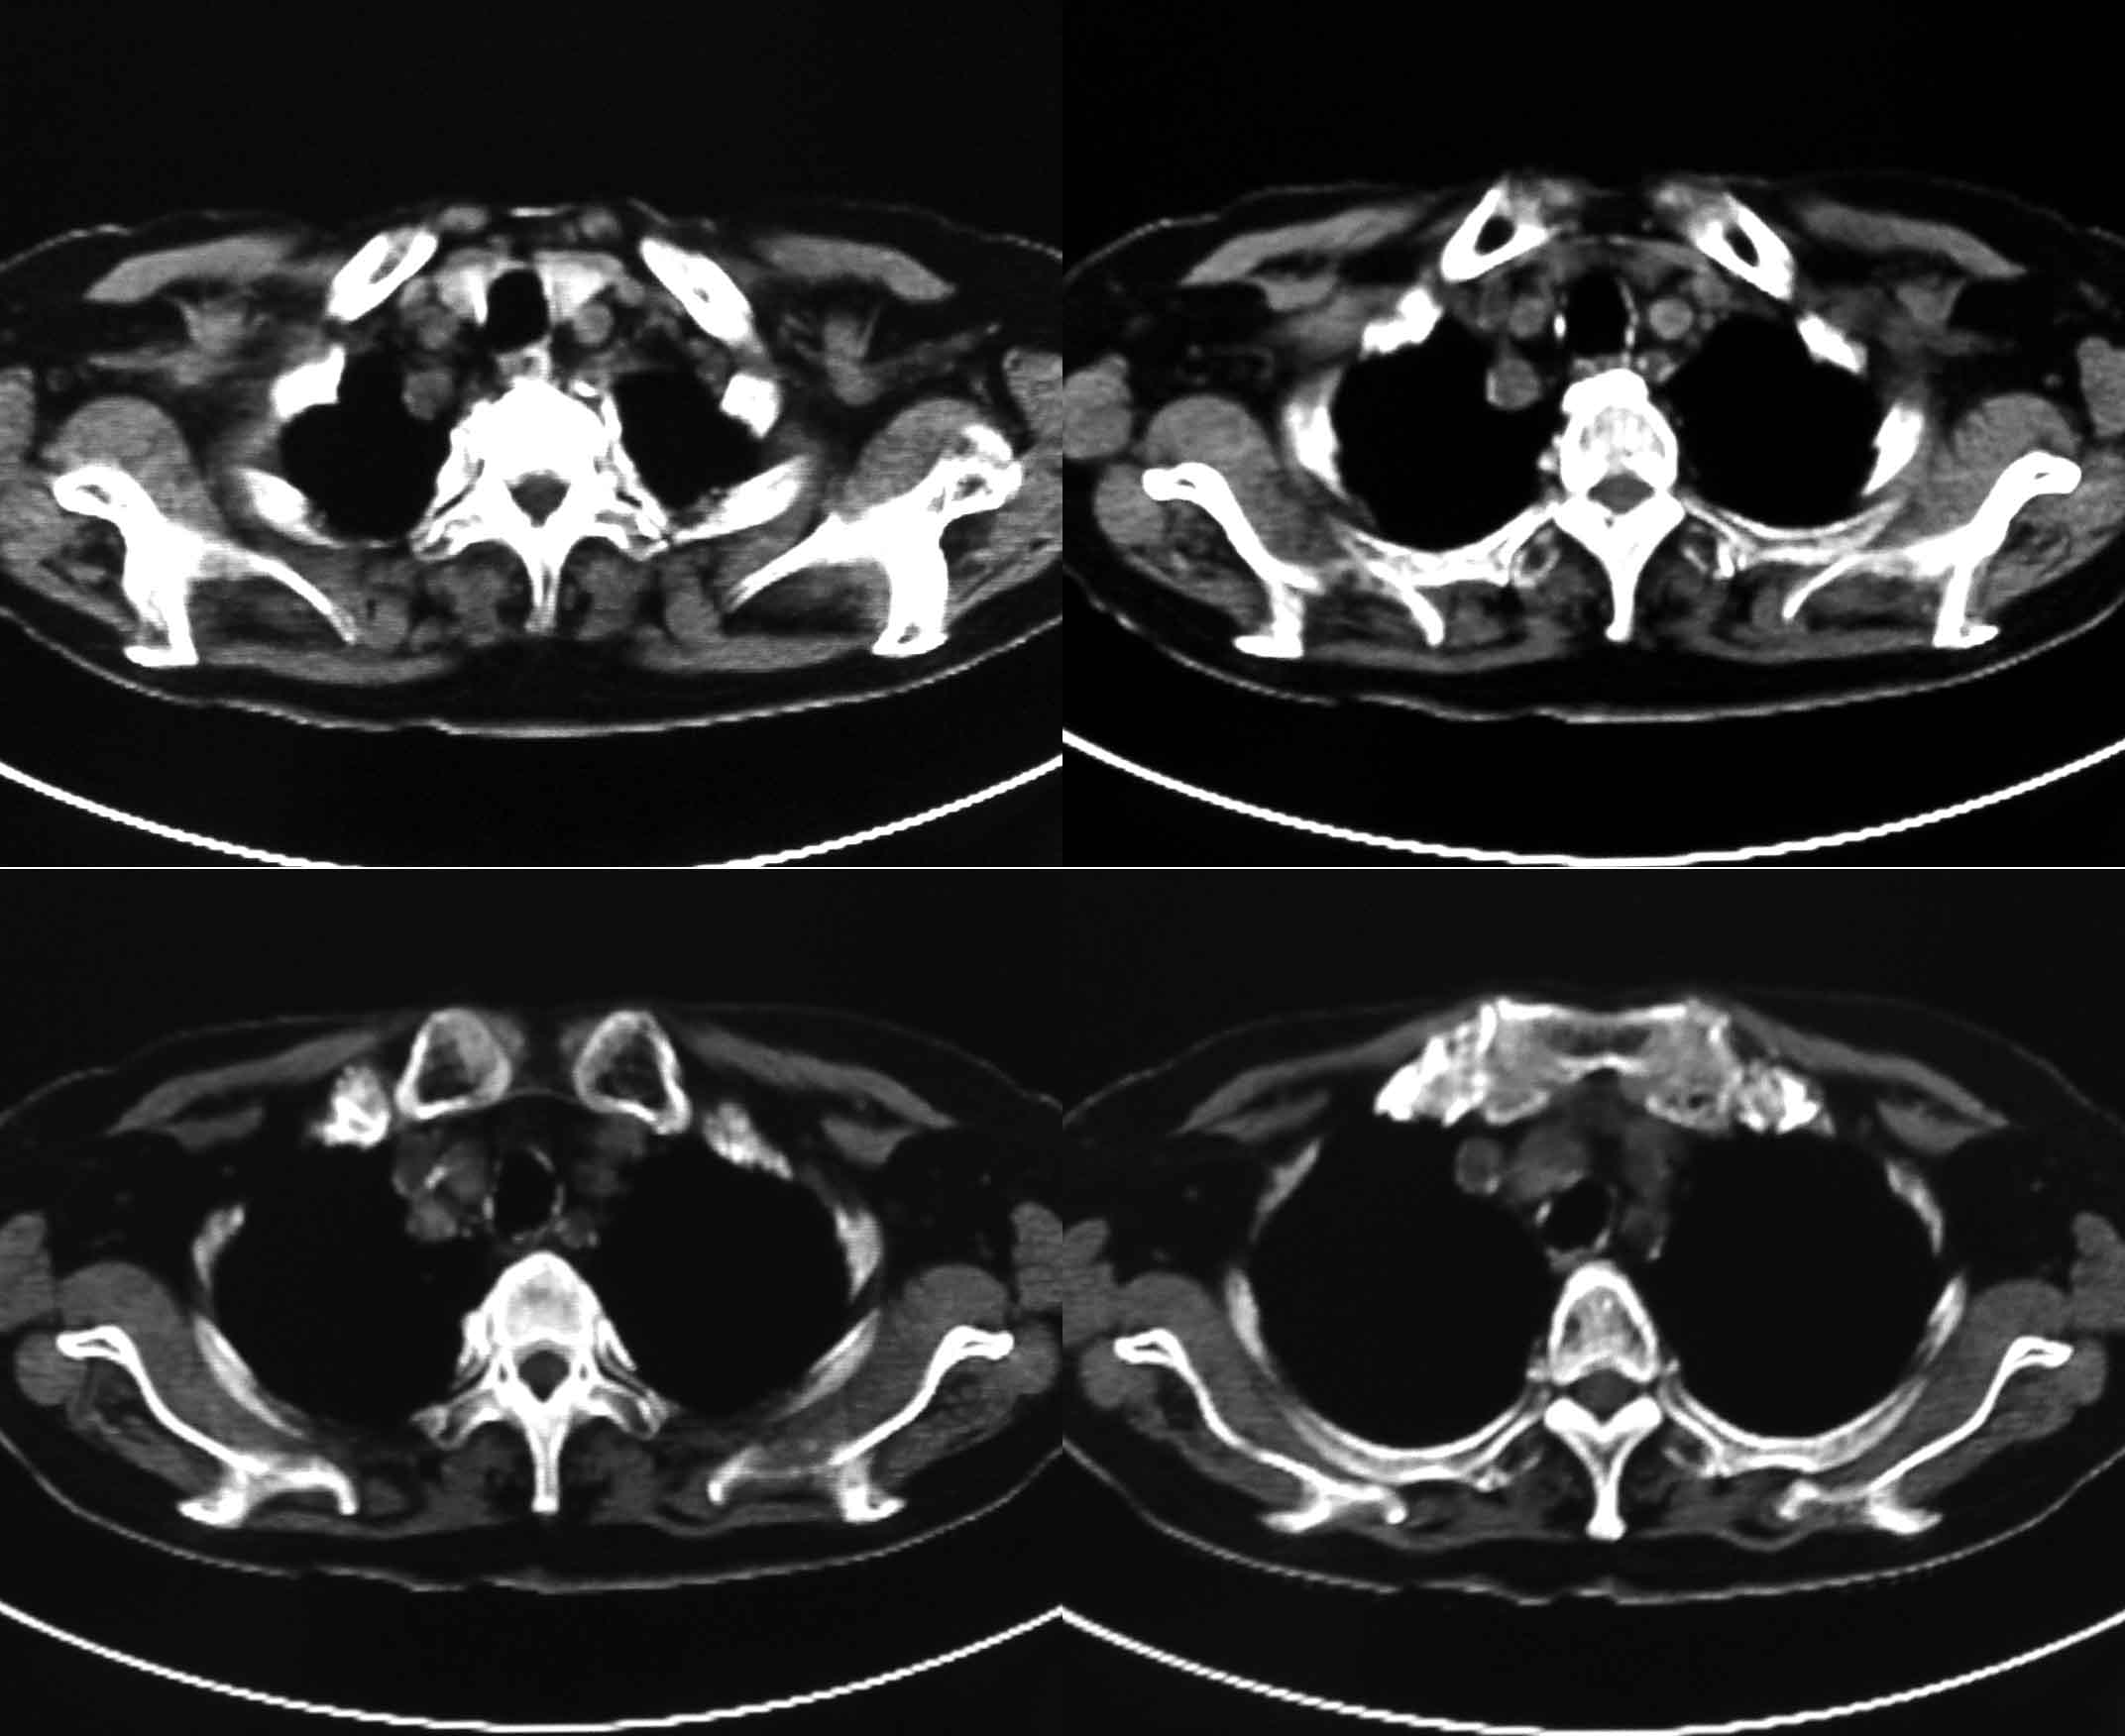

女69岁。时有咳漱、咳白色痰请老师们看看箭头所指是什么?ct值约-36.报告应该怎样写?谢谢!

说实话,图像质量一般,楼主所指为局部胸膜肥厚表现

考虑左后下胸内侧壁与胸膜之间脂肪影。

楼主所指为局限性胸膜肥厚

楼主所指为局限性胸膜肥厚  ct值是因为肺窗

局限性胸膜肥厚,心影增大,建议心超检查

胸膜下脂肪影。